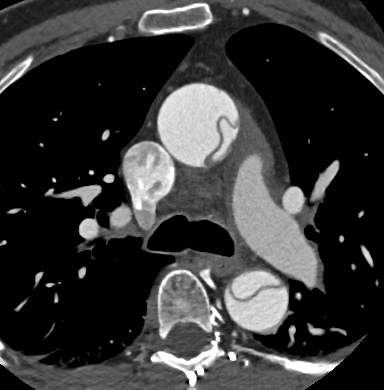

Fig. 3., 4., 5.: CT coronarography: Normal anatomy, volume rendered image and curved reformatted image Plaque causing stenosis on LAD coronary artery

The conventional imaging modality of the coronary vessels is cardiac catheterization (coronarography) which is still an absolute indication in acute coronary syndrome. During the examination besides identification of the symptom causing stenosis or occlusion (culprit lesion), it is also possible to perform dilatation with a balloon catheter or stent implantation to restore flow. If either of these procedures is carried out within 6 hours of symptom onset, myocardial tissue dearth can be prevented or minimalized. Coronarography of patients with stable angina is only recommended if a high risk of coronary disease persists clinically. CT coronarography can replace cardiac catheterization in low and medium risk patient groups who present with angina-like chest pain. The examination has a very high sensitivity and negative predictive value for coronary disease; therefore, it is a sensitive screening tool for patients who present with chest pain as a symptom of coronary stenosis. It can also uncover alternative diagnoses for chest pain syndromes. CT examination is not only good in representing the vascular lumen, but it can also detect non-stenosing but vulnerable (lipid rich) plaques by showing a special morphologic appearance. These lesions might remain hidden during coronarography, producing false negative results with regard to an existing significant atherosclerotic involvement.